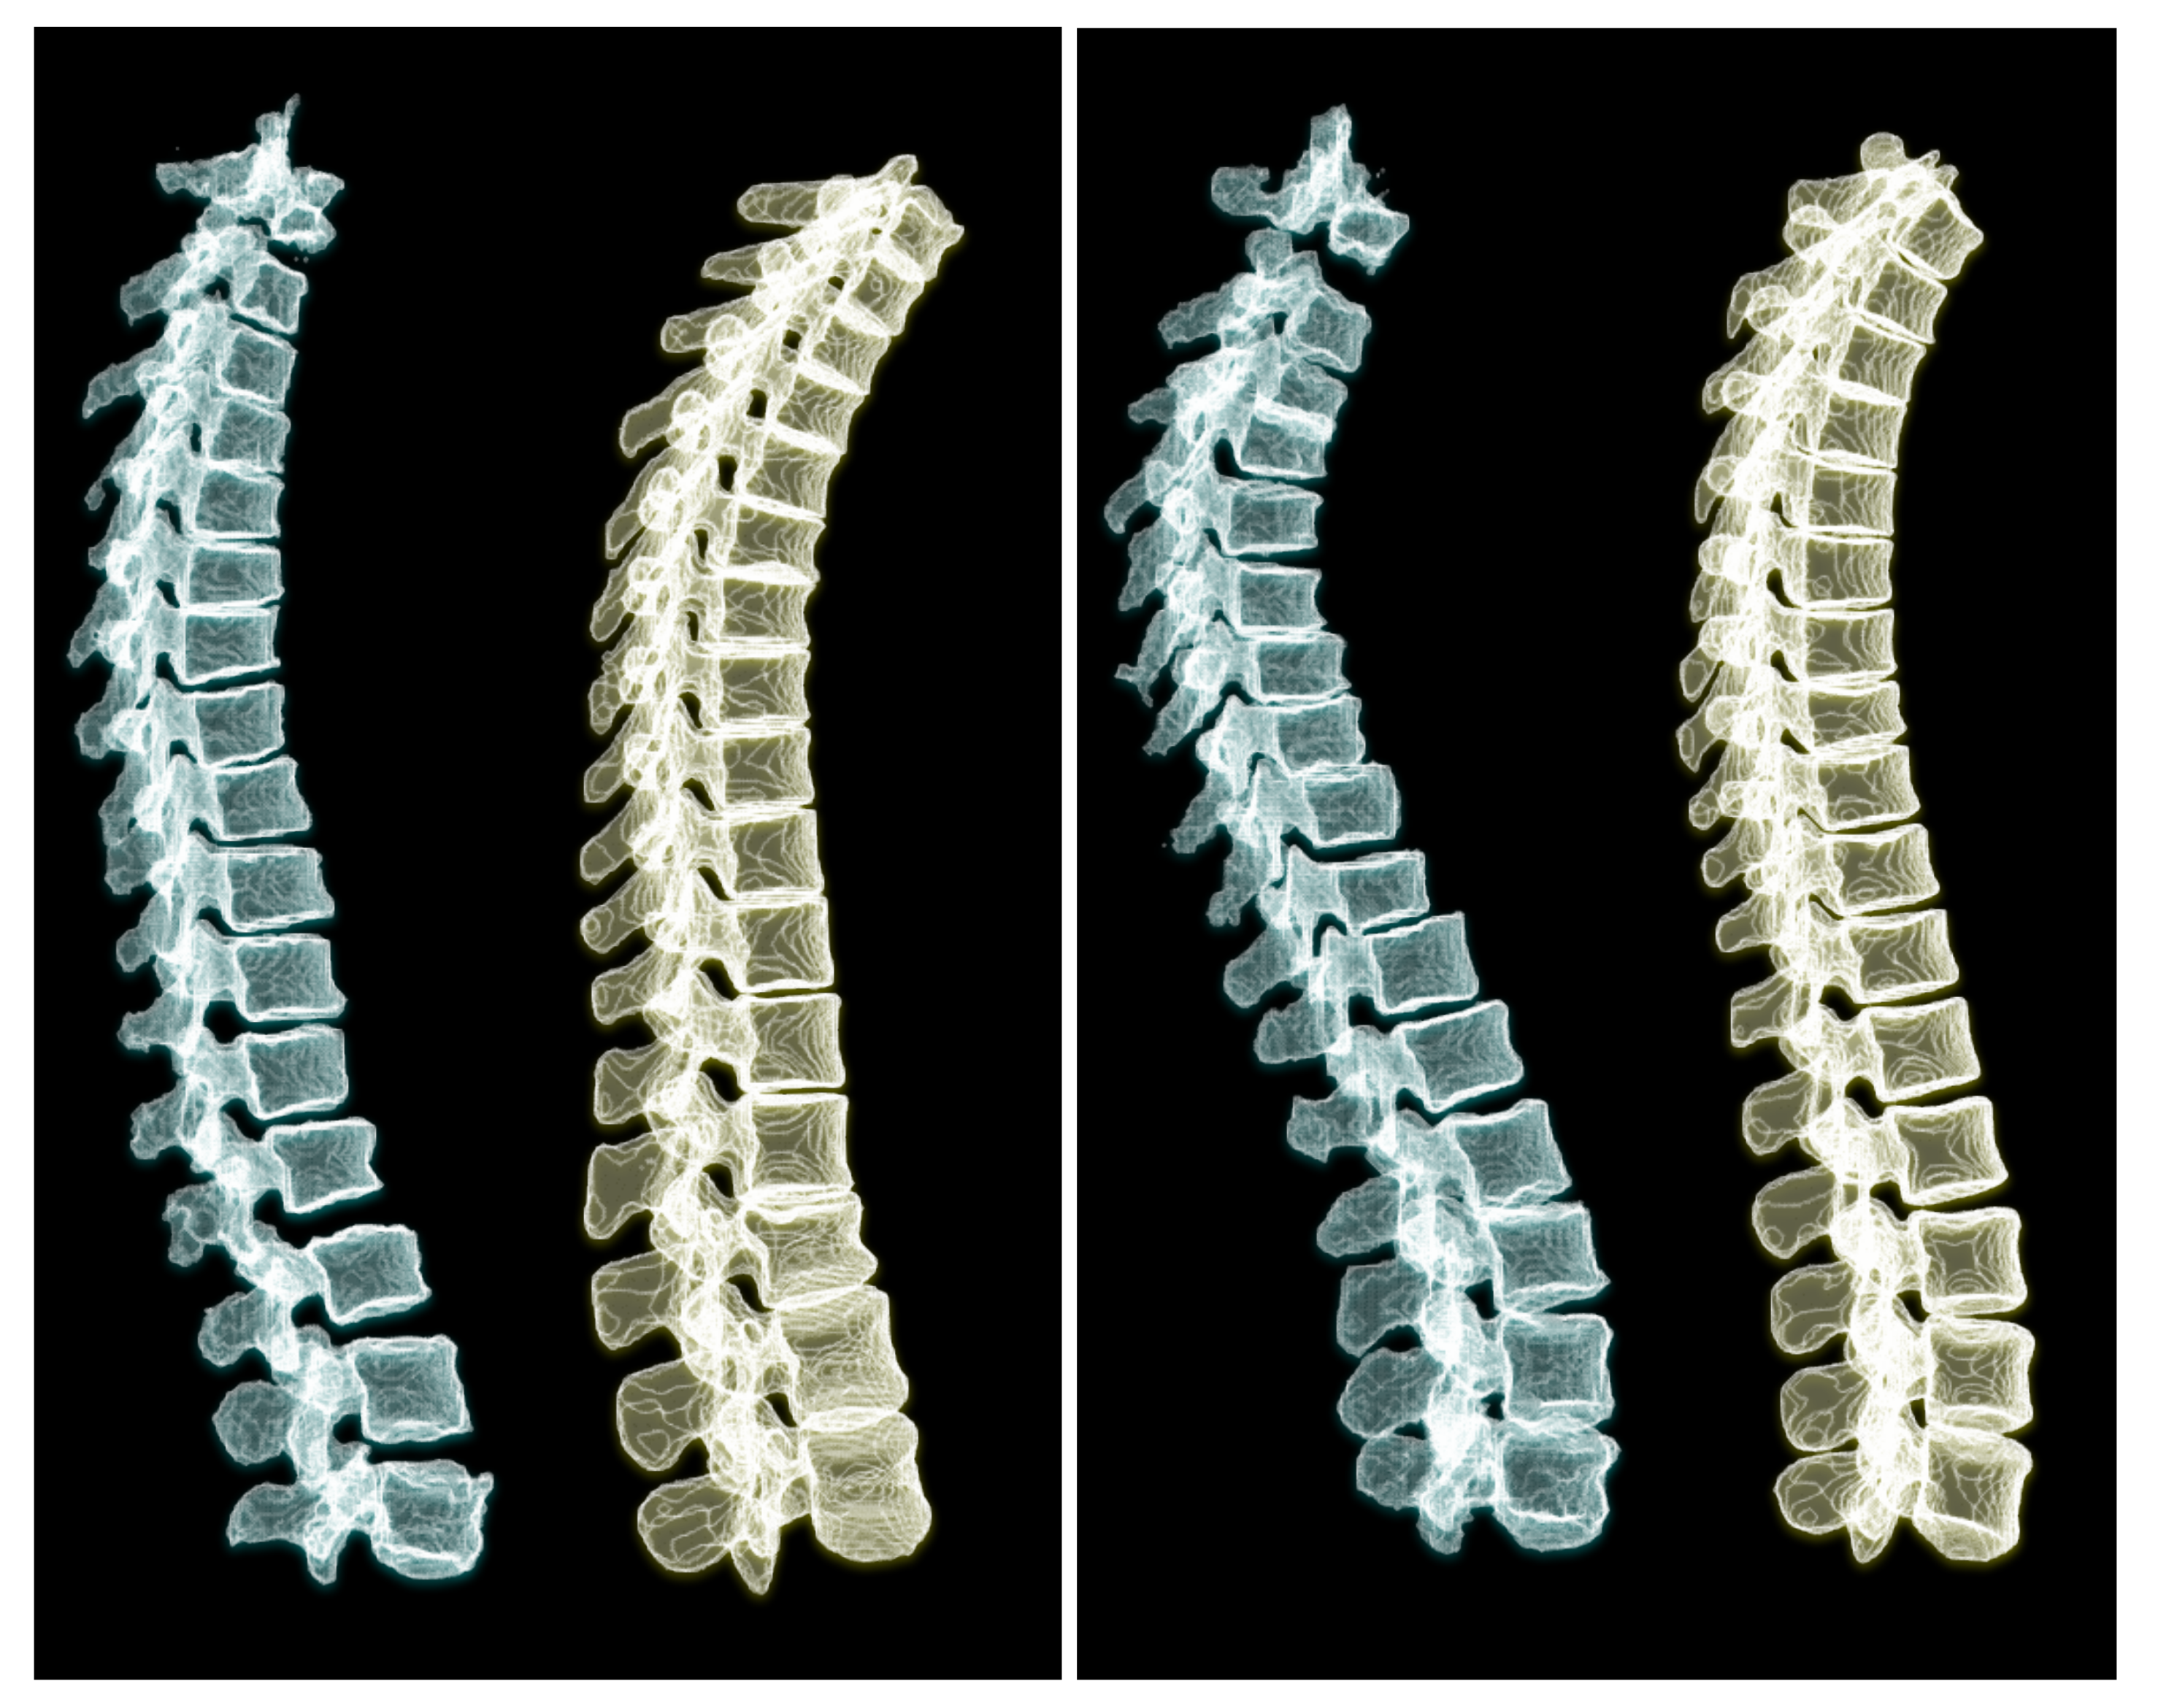

To appreciate the difference of spine posture in the standing and lying down positions, we illustrate the two cases we used in this experiment in Figure 12. The spine postures reconstructed from radiographs in upright standing position are depicted on the left and the ones from CT are depicted on the right side of the figure.

Figure 12. Comparing 3D reconstructions of the standing spinal posture from clinical radiographs (left, green) to the spinal posture of the same patient in lying-down position from CT imaging (right, yellow) in two different patients. In the upright-standing posture the spine is under natural weight bearing, which leads to a different spine curvature.